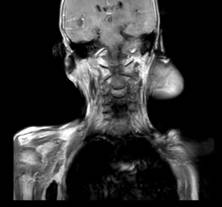

Hình ảnh khối u trên phim cộng hưởng từ